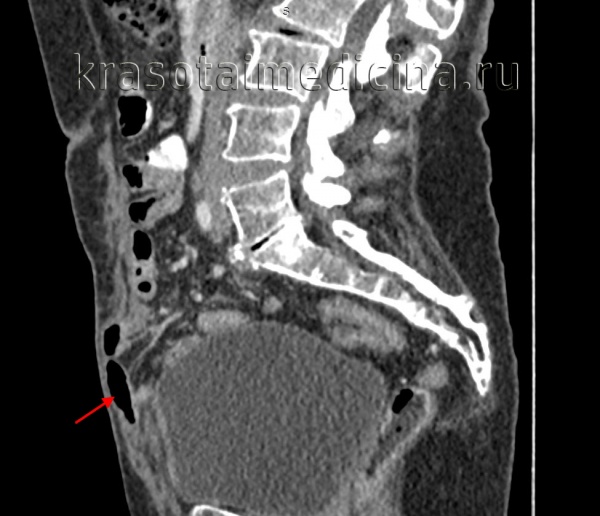

Пролабирование клетчатки